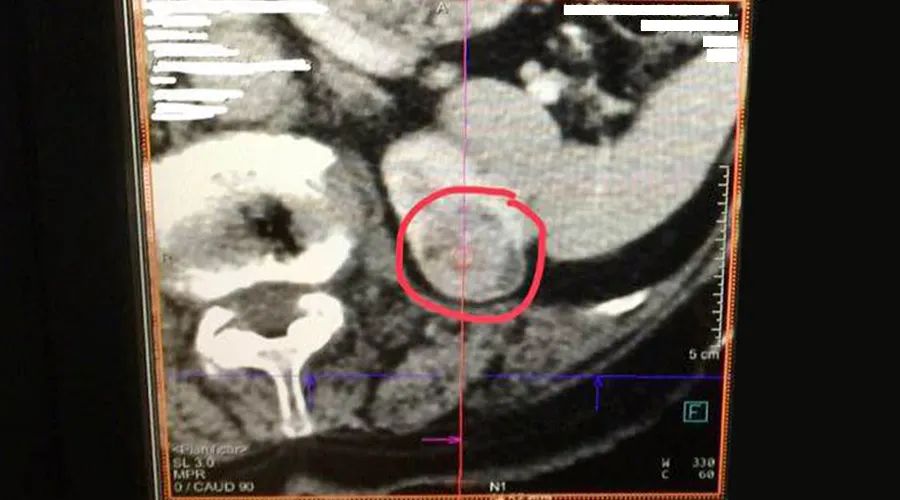

肿瘤位于肾脏,直径为2cm。主刀医生在CT的引导下,使用赛诺微SS-MWA-1531C微波天线进行单针消融(75w,10min),术后形成一个非常接近球形的直径为3cm的消融区域。整个消融过程很顺利,Dophi™ M150E微波消融系统在术中表现出来良好的可控性。手术结束后,医生边看术后影像资料边对我们说道,“赛诺微Dophi™ M150E微波消融系统表现出很好的可控性和精准性!消融后,病灶周围的血管等组织保存完好。”

术中影像资料